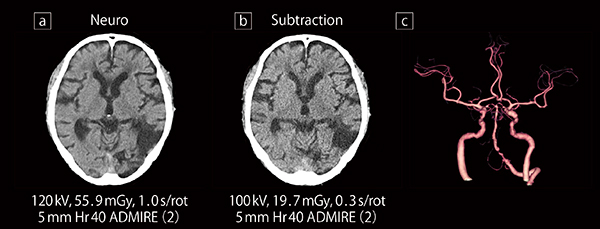

myExam Companionの適用例:頭部CT検査における撮影条件の変更

a:脳実質の評価を目的とした頭部単純CT(通常線量)

b: 頭部3D-CTAのサブトラクション処理を目的とした単純撮影(低線量・高速撮影)

c:3D-CTA画像

さらに,低管電圧撮影による造影剤量や被ばく線量の低減も重要だ。庄司係長は,「出血例などでCT撮影後に血管撮影を行う可能性があることを考慮すると,緊急検査時の造影剤量は最低限に抑えることが望ましく,SOMATOM X.citeで低管電圧撮影が行えることは大変有用です。また,被ばく線量低減の効果も大きく,ADMIREやTin filterにより,頭部で約20〜25%,体幹部で約40〜50%の被ばく線量を低減できています」と評価している。